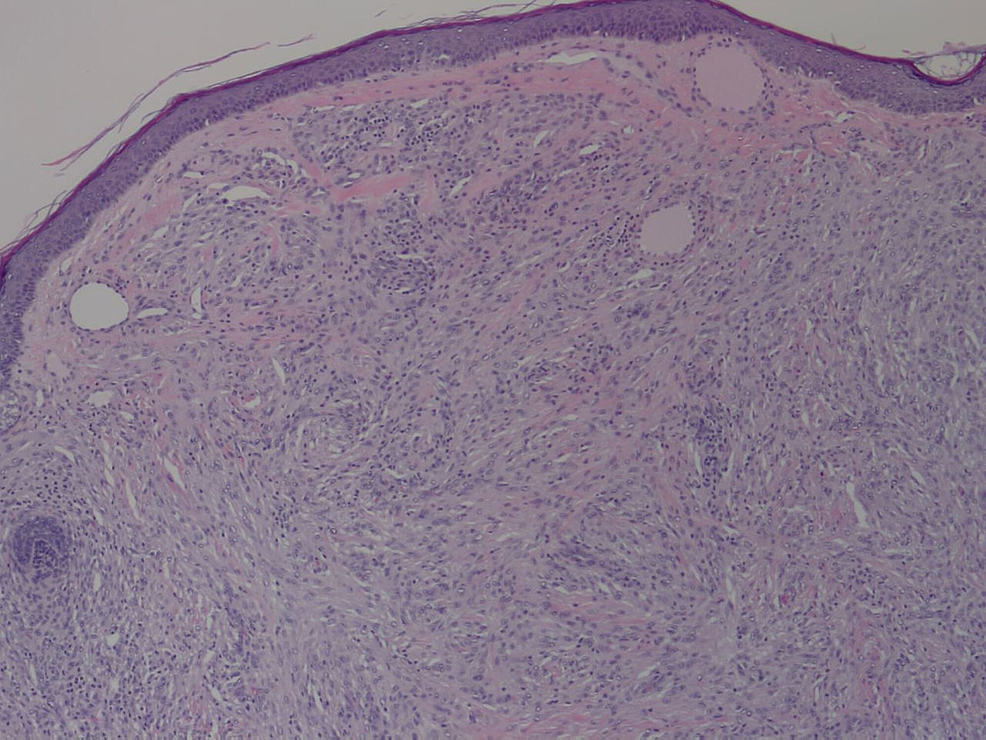

Spindle cells in plaque. Original magnification x S00. Download